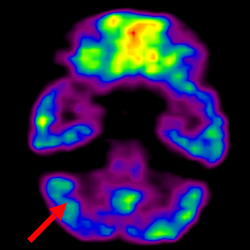

細胞治療前 PET CT 掃描顯示神經組織中的藍/黑色區域,表明腦癱引起的大腦損傷。